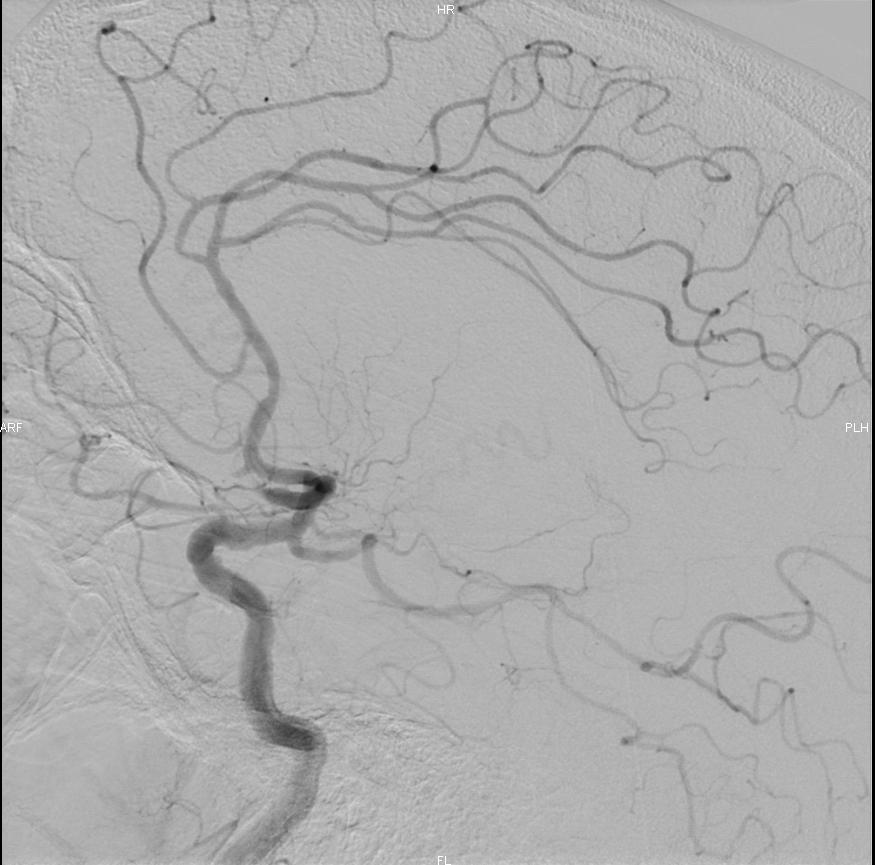

Lors de cette intervention réalisée par des radiologues spécialisés, un cathéter est inséré dans le réseau artériel, généralement par une piqure dans l’aine, et guidé jusqu’aux artères du cerveau, où il permet de retirer mécaniquement le caillot qui bloque la circulation sanguine à l’aide d’un stent et/ou d’un cathéter d’aspiration. Cette procédure vise à restaurer le flux sanguin vers la zone du cerveau affectée, minimisant ainsi les dommages cérébraux et améliorant les chances de récupération. L’intervention est réalisée sous contrôle radiologique en temps réel.

La thrombectomie intracrânienne a démontré une efficacité significative dans le traitement des AVC ischémiques. Techniquement, la recanalisation/réouverture de l’artère initialement bouchée est obtenue dans 80 à 90% des cas.

- Contrôle de la circulation sanguine : Un suivi d’imagerie (scanner ou IRM) sera effectué pour vérifier si la circulation sanguine a bien été rétablie et s’il n’y a pas de complications telles qu’un hématome (saignement dans le cerveau) ou une nouvelle occlusion.